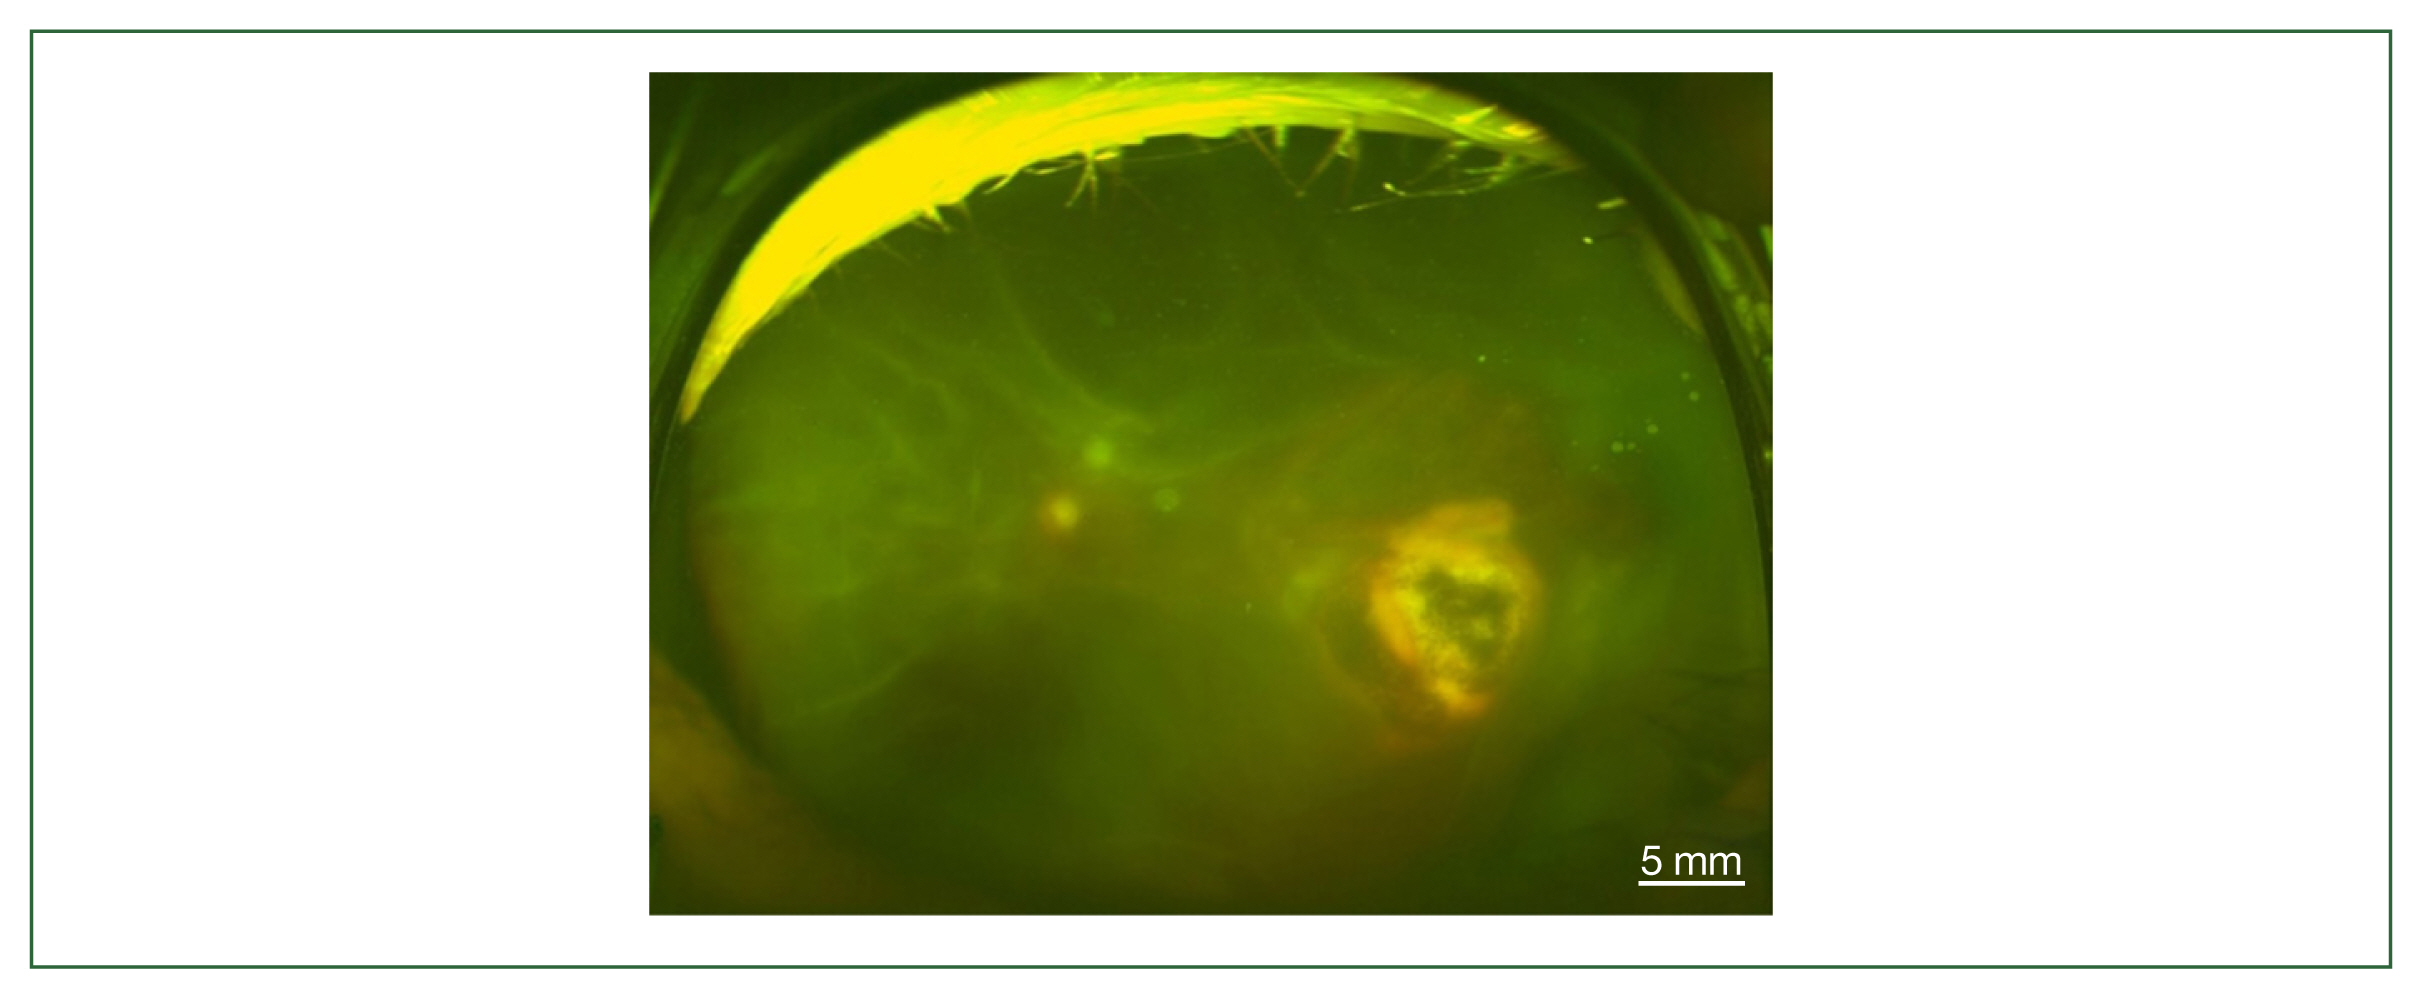

The 4 patients presented persistent unilateral visual disturbance 2–3 months before assessment. The ocular examination revealed that all study patients also exhibited unilateral panuveitis. Two patients (cases 1 and 2) did not show signs of chorioretinal scars, while the other 2 patients (cases 3 and 4) had preexisting scars on the retina and choroid. All of them showed an initial decimal visual acuity between 0.1 and 0.5. The ophthalmic analysis also revealed active retinochoroiditis in the 4 patients (Fig. 1) and papillitis and periphlebitis in cases 1 and 4, which were more evident by fundus fluorescein angiography (Fig. 2). All study patients also exhibited vitritis and anterior uveitis. Three patients (cases 1, 3, and 4) who underwent vitrectomy for diagnostic and therapeutic reasons had negative cytology for lymphoma cells. The remaining patient (case 3) had re-vitrectomy combined with scleral encircling for total retinal detachments developed later (Fig. 3). Only 1 patient (case 1), who was previously diagnosed with acute retinal necrosis (ARN) in a local ophthalmology clinic, received a systemic steroid treatment (60 mg per day) for posterior uveitis before visiting the Eye Center at the Seoul St. Mary Hospital, Catholic University. None had received any medication (including antibiotics) before the examination.